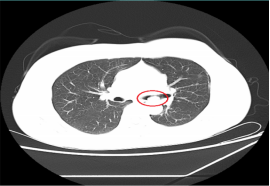

近年来,学生肺结核发病率呈现增多趋势,青年学生艾滋病例数量增长迅速。为了进一步做好学校结核病和艾滋病防治工作,连日来,我院感染性疾病科走进璧山中学东林校区、双星校区、枫香湖校区,开展了结核病和艾滋病防治知识健康科普系列活动。 活动现场,医护人员通过知识讲座、发放资料、现场互动等多种形式,让学生们深入了解关于结核病和艾滋病的致病原理、发病状况、传播途径、防治措施等。用生动的事例、大量的数据,让同学们懂得防治肺结核和艾滋病的重要性,筑起结核病和艾滋病防护墙。活动最后,感染科医护人员还为同学们进行了结核菌素试验(PPD)筛查。 此次活动,进一步提高了我区师生防治结核病和艾滋病的意识和自我保护能力,有助于提早发现结核病人,防止新生带病入学,为师生的身体健康提供了保障;也让同学们自觉提高了个人卫生习惯,切实为学习生活营造一个健康、文明、安全、和谐的良好氛围。